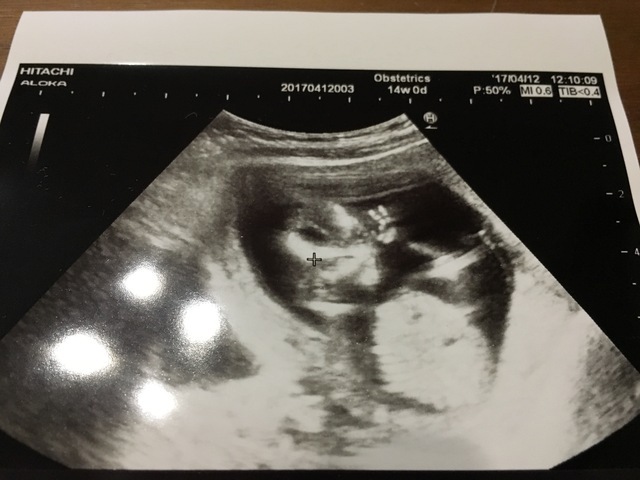

14週0日(14w0d・女の子)|ひろみんみん さん(28歳)

エコー写真撮影時のエピソード:

エコー写真を先生から渡された瞬間に、ピースをしている(ように見える)我が子に気づいてびっくりしました。

見れば見るほどピースに見えて、家族や友達にも見せています。愛嬌のある子が生まれてくるのだろうと楽しみにしています。